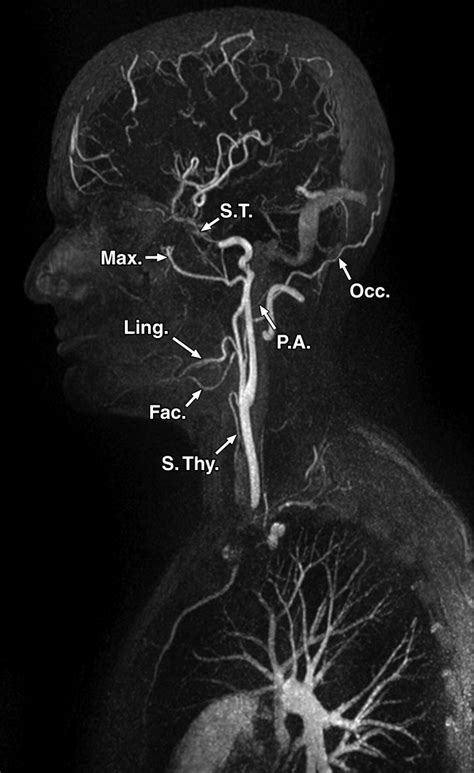

• Cerebral Angiography: This involves imaging the blood vessels in the brain and neck. It is used to detect conditions like aneurysms, arteriovenous malformations (AVMs), and strokes.

Advances in medical technology have significantly enhanced the effectiveness and safety of Angio procedures. Modern imaging techniques, such as computed tomography (CT) angiography and magnetic resonance (MR) angiography, provide high-resolution images of blood vessels without the need for invasive procedures. These non-invasive alternatives are particularly useful for patients who may not be suitable candidates for traditional Angio procedures.